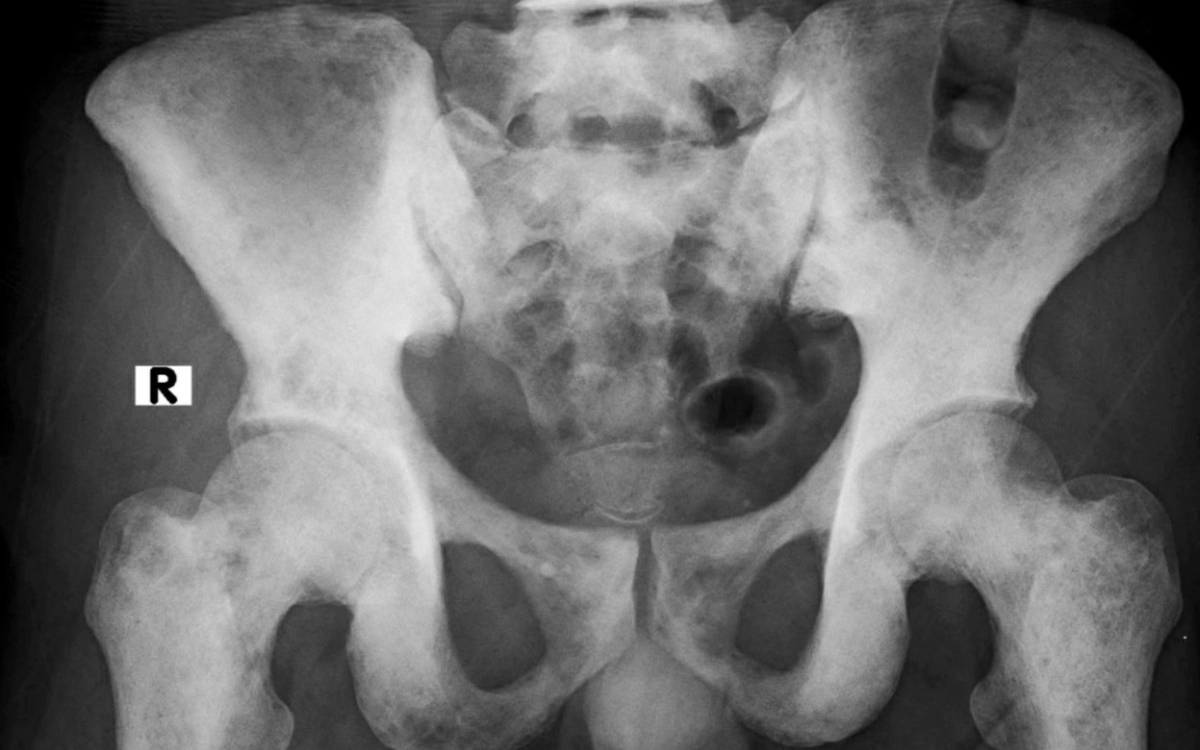

2. Radiografia

Radiografia este una dintre primele metode utilizate pentru evaluarea oaselor. În fazele timpurii ale necrozei avasculare, aceasta poate să nu arate modificări semnificative, motiv pentru care diagnosticul nu trebuie exclus doar pe baza unei radiografii normale. În stadiile avansate, însă, radiografia poate evidenția colapsul osos, deformarea articulației sau apariția artrozei secundare.